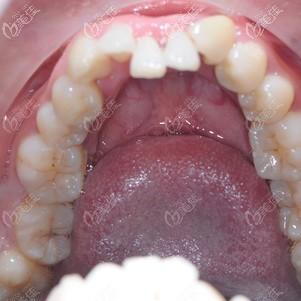

门牙往里凹图片,牙齿内扣图片

两颗下门牙往里凹在东莞牙易美带上时代天使牙套后同事们都没人看出来

牙齿内扣图片

门牙往里凹

门牙往里凹图片 凹陷

门牙内凹

牙齿内凹图片